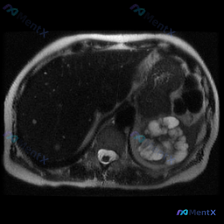

今天看到一份影像资料,觉得很有警示意义,整理一下思路和大家分享。 --- 先看明确的影像表现 用户提供的是腹部MRI(T2加权轴位),影像分析里明确给出了这些客观发现: 1. 左肾区域:有一个巨大的囊性占位,取代了正常肾实质,是多房性、分隔状的,里面是T2高信号液体,边界清,膨胀性生长,把周围组织推...